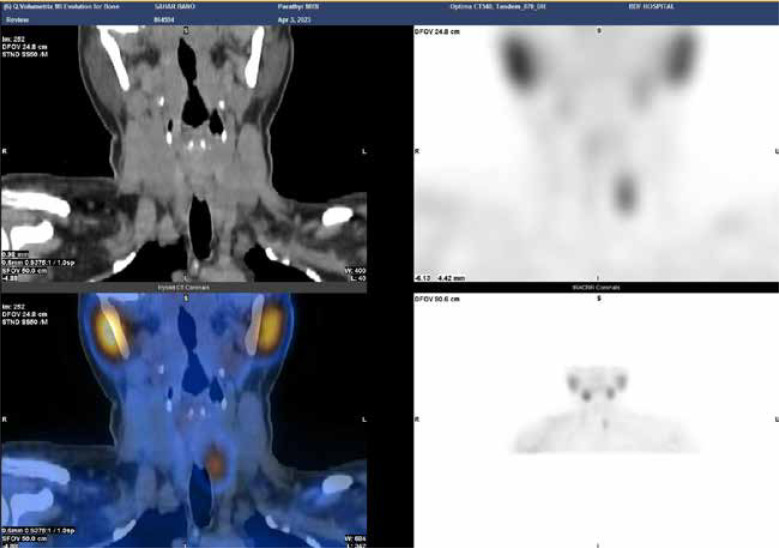

Purpose: Primary hyperparathyroidism is mainly caused by parathyroid adenomas. Preoperative imaging can be performed using different imaging modalities, e.g. ultrasound (US), radionuclide scanning, magnetic resonance imaging, and computed tomography, often used in combination. Currently, US-guided blue dyes, especially methylene blue (MB) injection, are used to identify parathyroid tumours.

Material and methods: This was a retrospective study of 228 patients. Preoperative ultrasound, scintigraphy, and bio-chemistry were performed on all patients, and fine-needle aspiration procedures were performed on suspected patients. Using preoperative US-G injection with MB dye, target tumours were injected in all cases.

Results: A total of 163 patients were female and 65 were male. The mean age was 42.5 years. US was positive in 203 (89%) cases, 25 (11%) were negative, and all had a positive sestamibi scan (100%). US-G needle injections with MB dye of target tumours were successful in all cases. The average diameter of the lesions was 18 mm. All had positive intraoperative identification of parathyroid adenoma and MB staining (100% accuracy, 100% sensitivity, and 100% specificity). Operating time (min ± SD) was 22.7 ± 11.5 minutes, and the success rate was 100%. All were parathyroid adenomas histologically. Intraoperative parathormone hormone decreased in all patients. In postoperative follow-up, all were normocalcaemic with no local or systemic complications.

Conclusions: Localisation of small parathyroid adenomas by US-guided blue dye injection is a safe, simple, and useful tool when performing parathyroidectomy with no complications.